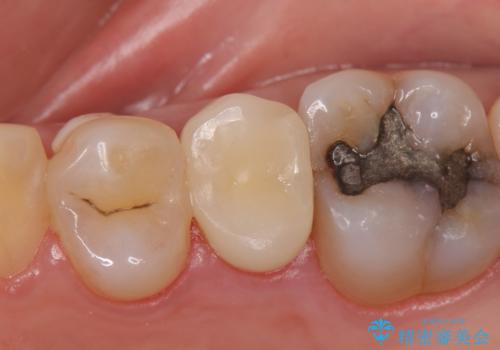

見た目では問題がなさそうでも、レントゲン撮影・診査を行うと状態が悪くなっていることがあります。